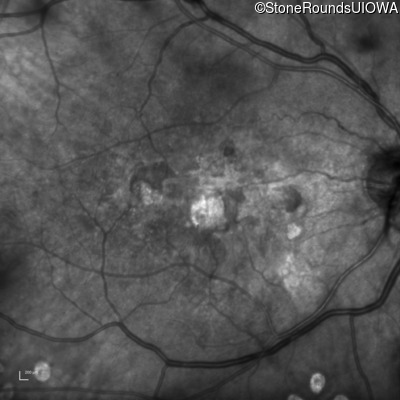

Malattia Leventinese (IIJ)

Malattia Leventinese (IIJ)

This 43 year old woman has experienced a gradual reduction in her central vision for the past 3 years.

| Malattia Leventinese | EFEMP1 | Arg345Trp CGG>TGG | AD |